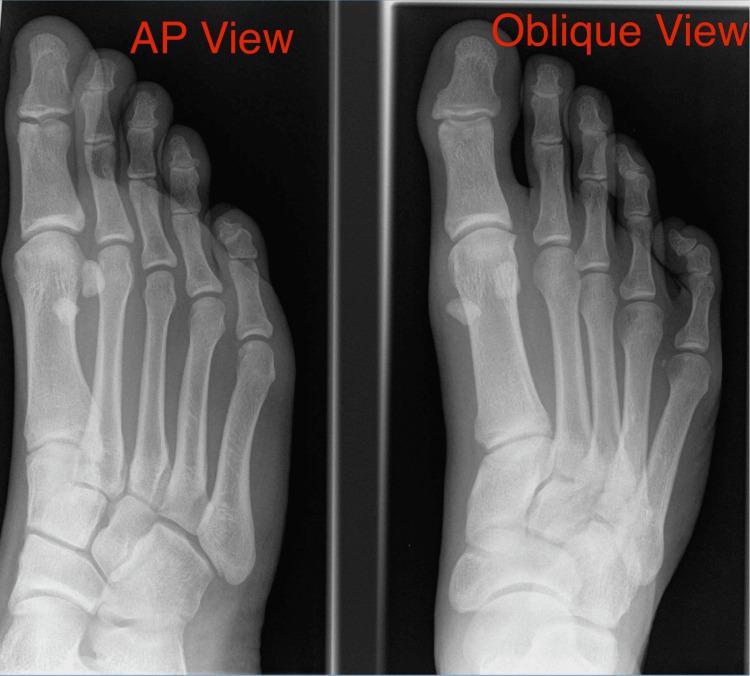

Background "Turf toe" is a classical capsuloligamentous injury to the plantar surface of the metatarsophalangeal (MTP) joint of the great toe. The name is synonymous with injuries sustained on artificial turf or hard grounds. The classical injury pattern is a hyperdorsiflexion injury with an axial load. The outcomes of these injuries are unpredictable and there are no clear guidelines for the management of these injuries. These injuries are debilitating and can lead to long-term problems and inability to return to pre-injury activity level if missed. We present a long-term surgical follow-up of severe grade 3 turf toe injuries. Methods In the period from 2011 to 2022, we treated 20 patients with turf toe/MTP joint instability. There were 10 football injuries (50%), six running injuries (30%), two gymnastic injuries (10%), one motorcycle injury (0.5%), and one was a ballet dancer (0.5%). All the grade 1 and 2 injuries were treated conservatively with rest, ice application, and splinting of the toe. Grade 3 injuries were treated surgically and strict rehabilitation protocol was followed. Results The mean age at surgery was 32.7 years and the average patient follow-up was 7.5 months after surgery. The Manchester-Oxford Foot Questionnaire (MOXFQ) score showed a statistically significant improvement from a mean of 73.0 (median = 75) preoperatively to 28.1 (median = 28.6) postoperatively (median improvement = 46.4, P = 0.022). Similarly, there was a significant improvement in pain score, which showed an improvement from a mean of 72.9 (median = 70.0) preoperatively to a mean of 22.9 (median = 25.0) postoperatively (median improvement = 51.3, P = 0.022). Conclusion Turf toe is a serious injury that may prevent a high percentage of patients from resuming their previous physical activities. The correct identification, classification, and grading of the first MTP joint instability helps in decision-making and achieving good surgical outcomes.

背景 “草皮趾” 是一种累及拇趾跖趾(MTP)关节跖面的典型关节囊韧带损伤。该名称与在人工草皮或硬地面上遭受的损伤同义。典型的损伤模式是轴向负荷下的过度背屈损伤。这些损伤的预后不可预测,且对于这些损伤的处理尚无明确的指导方针。这些损伤会使人衰弱,如果漏诊,可能导致长期问题并无法恢复到受伤前的活动水平。我们展示了对重度3级草皮趾损伤的长期手术随访结果。